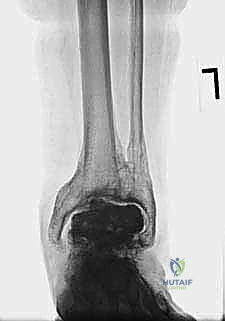

FIG 1 • Acute ( A ) and chronic ( B ) medial malleolus fractures. The former fractures occur due to an intraoperative technical error.

* Late (Chronic): Result from weakened bone architecture due to osteolytic cysts, or undue stresses applied to the malleoli from deformity or altered gait mechanics. Micro- or macromotion at the prosthesis-bone interface, particularly at the fibula, can also contribute.

FIG 1 • Acute ( A ) and chronic ( B ) medial malleolus fractures. The latter can occur from imbalance about the prosthesis with undue stresses.

The natural history of malleolar fractures is compromised by the limited bone available due to the prior implant. This reduces the surface area for healing, increasing the likelihood of nonunion. Nonunion can lead to a relative increase in malleolar length and subsequent ligamentous laxity, predisposing to instability and deformity. Once deformity is present, it creates abnormal stresses that further hinder union.